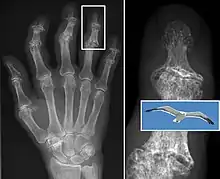

In smaller joints, such as at the fingers, hard bony enlargements, called Heberden's nodes (on the distal interphalangeal joints) or Bouchard's nodes (on the proximal interphalangeal joints), may form, and though they are not necessarily painful, they do limit the movement of the fingers significantly. Osteoarthritis of the toes may be a factor causing formation of bunions,[17] rendering them red or swollen.

Diagnosis is made with reasonable certainty based on history and clinical examination.[41][42] X-rays may confirm the diagnosis. The typical changes seen on X-ray include: joint space narrowing, subchondral sclerosis (increased bone formation around the joint), subchondral cyst formation, and osteophytes.[43] Plain films may not correlate with the findings on physical examination or with the degree of pain.[44] Usually other imaging techniques are not necessary to clinically diagnose osteoarthritis.

In 1990, the American College of Rheumatology, using data from a multi-center study, developed a set of criteria for the diagnosis of hand osteoarthritis based on hard tissue enlargement and swelling of certain joints.[45] These criteria were found to be 92% sensitive and 98% specific for hand osteoarthritis versus other entities such as rheumatoid arthritis and spondyloarthropathies.[46]

Severe osteoarthritis and osteopenia of the carpal joint and 1st carpometacarpal joint.

Primary osteoarthritis of the left knee. Note the osteophytes, narrowing of the joint space (arrow), and increased subchondral bone density (arrow).

Both primary generalized nodal osteoarthritis and erosive osteoarthritis (EOA, also called inflammatory osteoarthritis) are sub-sets of primary osteoarthritis. EOA is a much less common, and more aggressive inflammatory form of osteoarthritis which often affects the distal interphalangeal joints of the hand and has characteristic articular erosive changes on x-ray.[51]